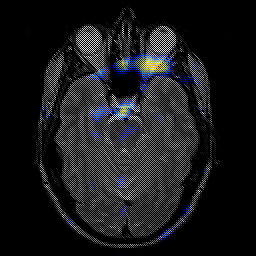

glioma overlay -- Slice #9

[Home][Help][Clinical] Slice 9